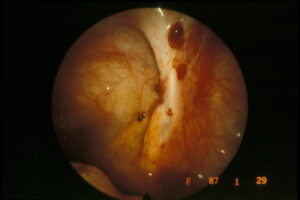

Identificare endometriosi senza laparoscopia

Due distinti team di ricerca, provenienti da Australia e Giordania l'uno e Belgio e Ungheria l'altro, stanno sviluppando un test...